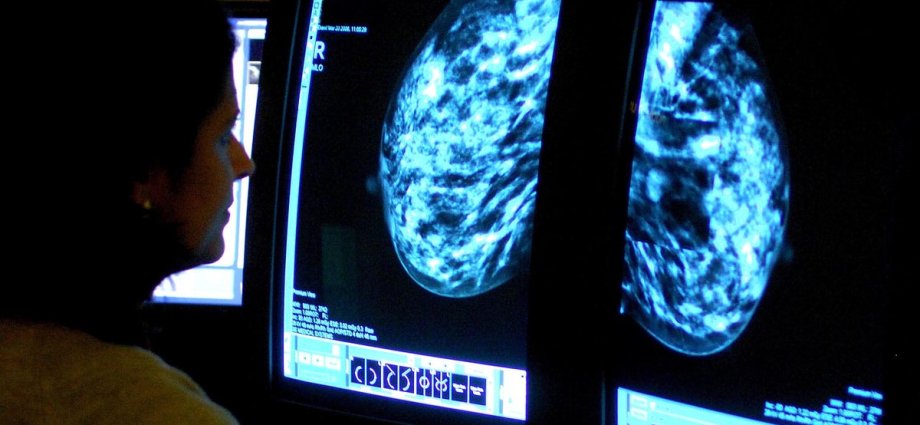

Dense breasts, occurring in about 10% of women, contain more fibrous and glandular tissue and less fatty tissue, obscuring potential tumours during standard mammograms. Women with this type of breast tissue already face a four times greater risk of developing breast cancer.

At the moment, because denser breasts look whiter on mammograms, the usual mammogram scan cannot pick up all these cancers.

Early-stage cancers also appear white, meaning they are difficult to distinguish.